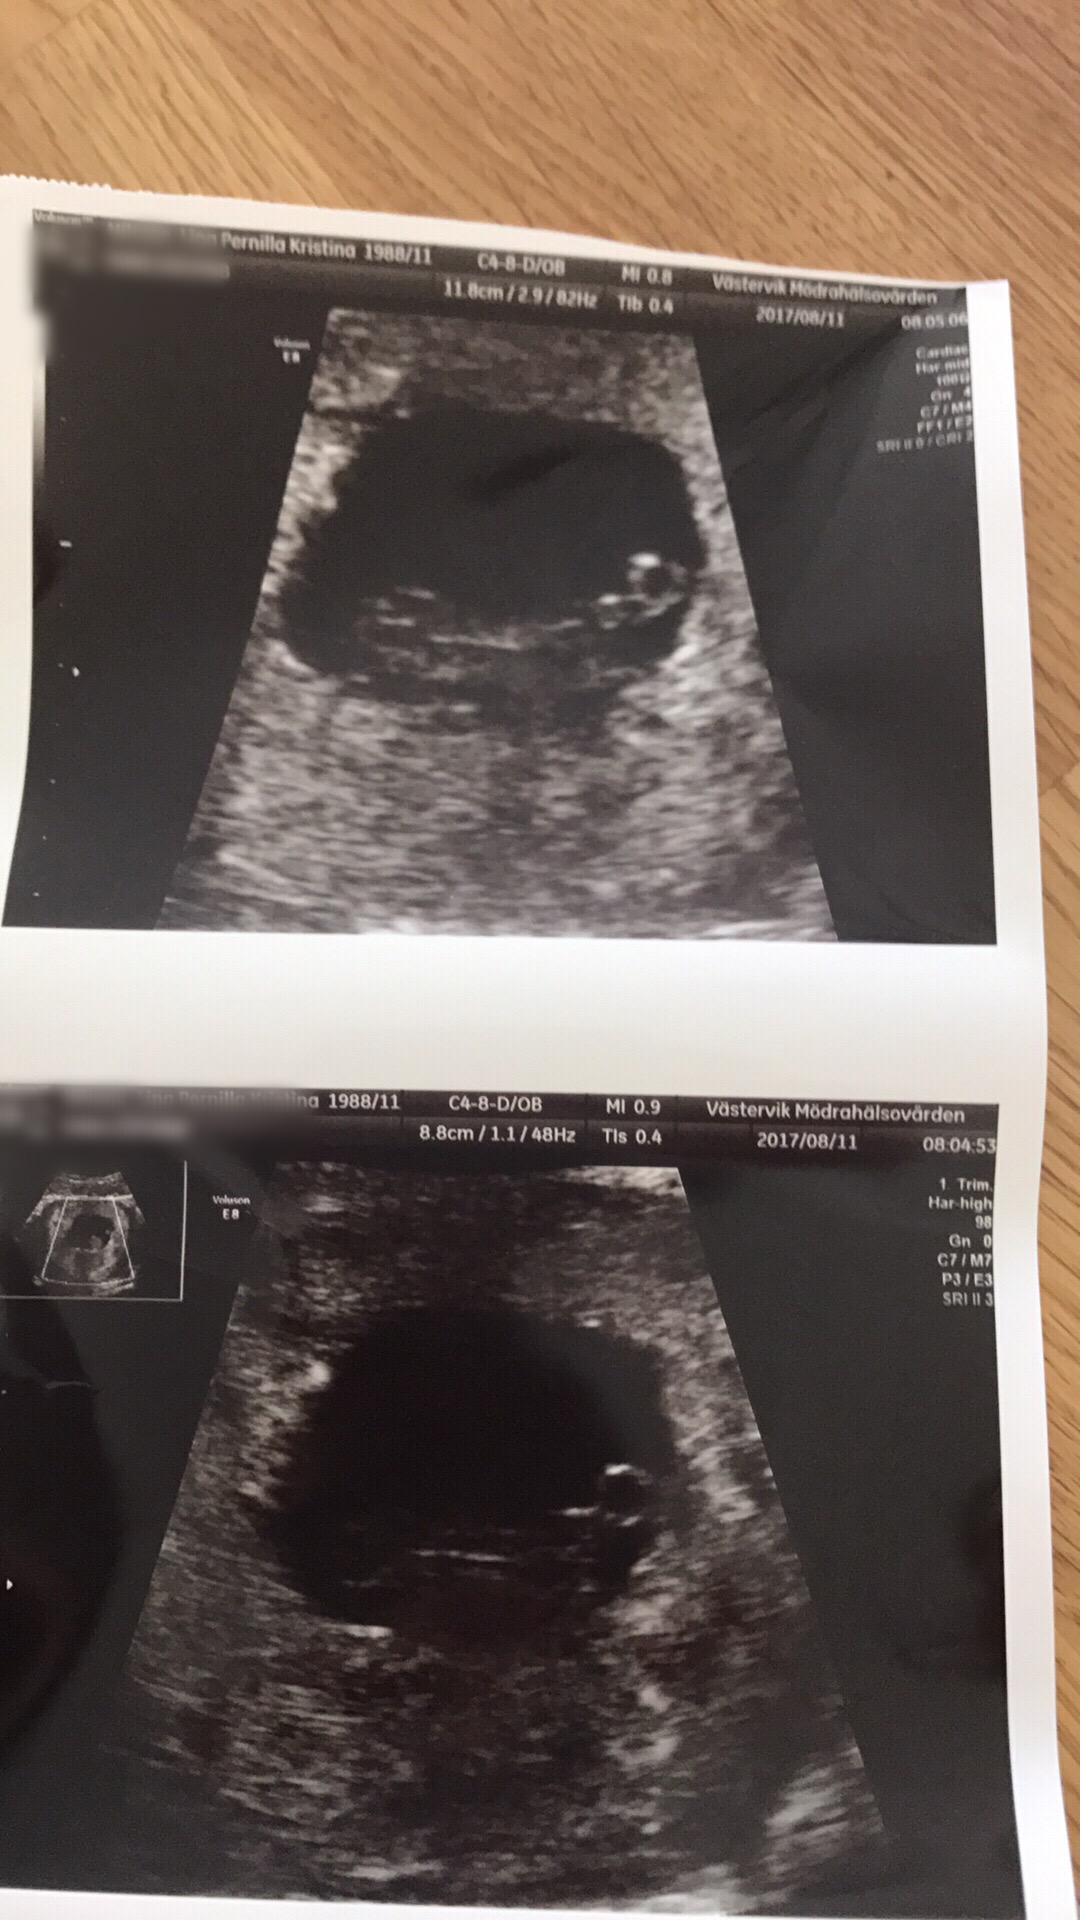

Det jag ser fram emot mest är att fixa i larvens rum. Som tur är får vi (förhoppningsvis) veta i slutet på oktober om det är en liten kille eller tjej som gömmer sig där inne (i min mage alltså, i rummet hoppas jag att det inte är någon som gömmer sig).